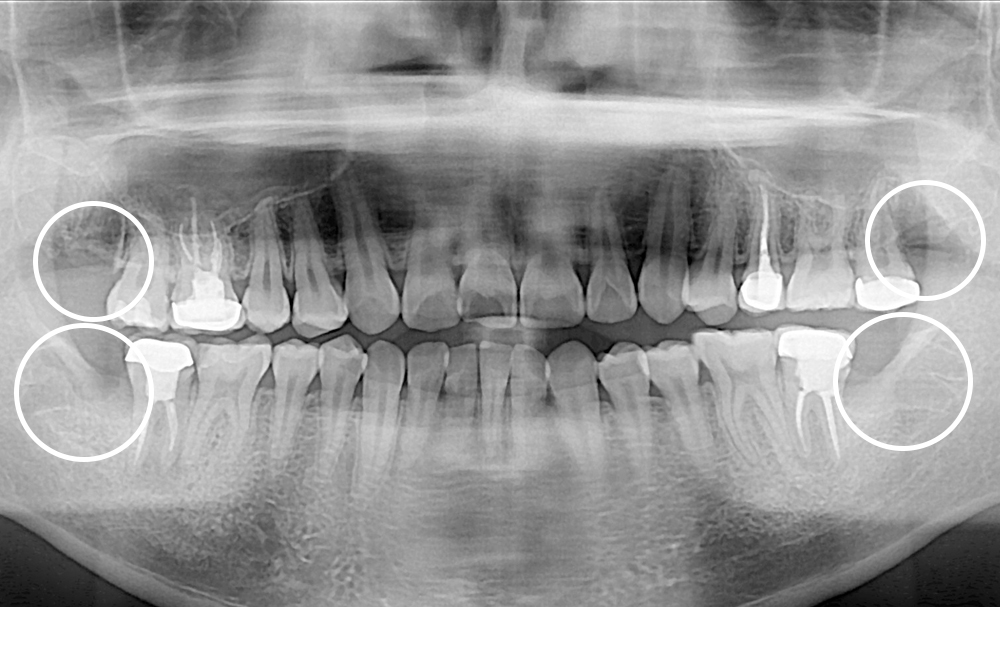

[사랑니] 매복 사랑니 발치

치료전 : 2020-05-18